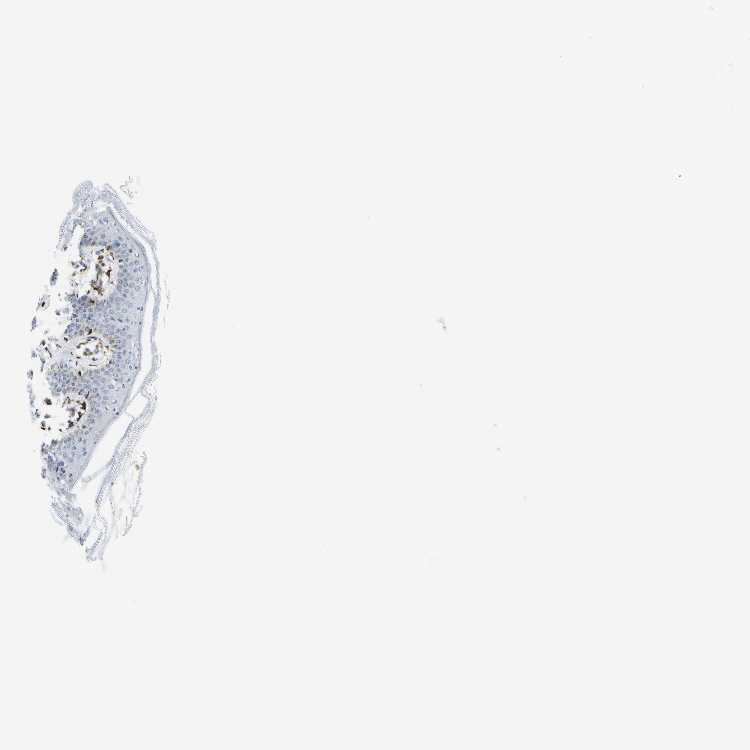

SKIN 2 - Antibody stainingi

Antibody staining in the annotated cell types in the current human tissue is reported as not detected, low, medium, or high, based on conventional immunohistochemistry profiling in selected tissues. This score is based on the combination of the staining intensity and fraction of stained cells.

Each image is clickable and will lead to virtual microscopy that enables deeper exploration of all samples and also displays staining intensity scores, fraction scores and subcellular localization as well as patient and tissue information for each sample.

Antibody HPA016807

Epidermal cells Low